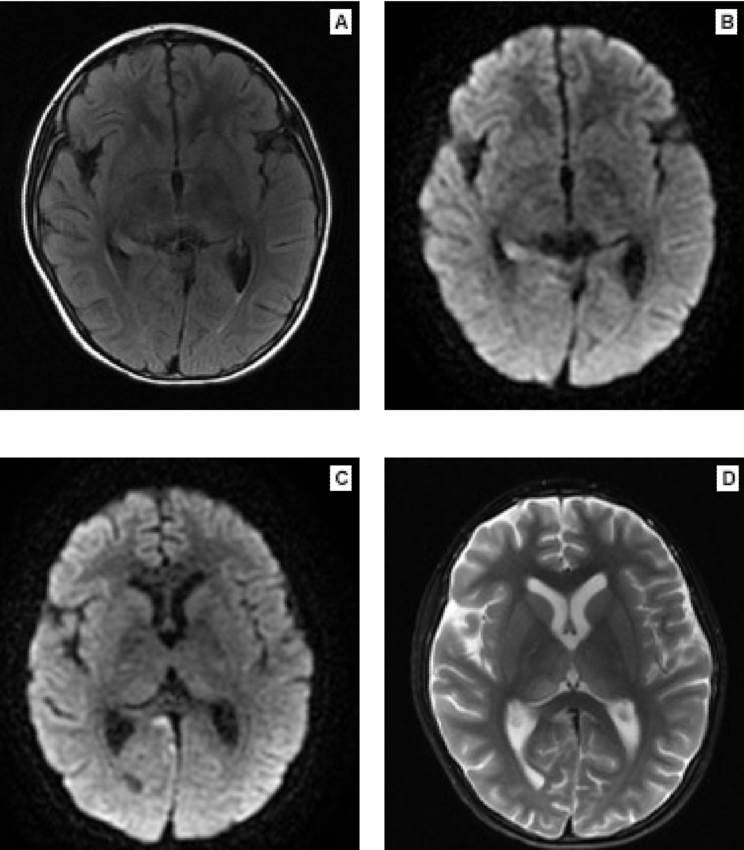

La encefalopatía límbica se caracteriza por cuadro súbito asociado a confusión, déficit de memoria, cambios de humor y, a menudo, convulsiones. El desarrollo subagudo de pérdida de memoria a corto plazo se considera el sello distintivo de este trastorno;7 los criterios diagnósticos se describen en el Cuadro 4 y los hallazgos por imagen de resonancia magnética cerebral se aprecian en la Figura 1.